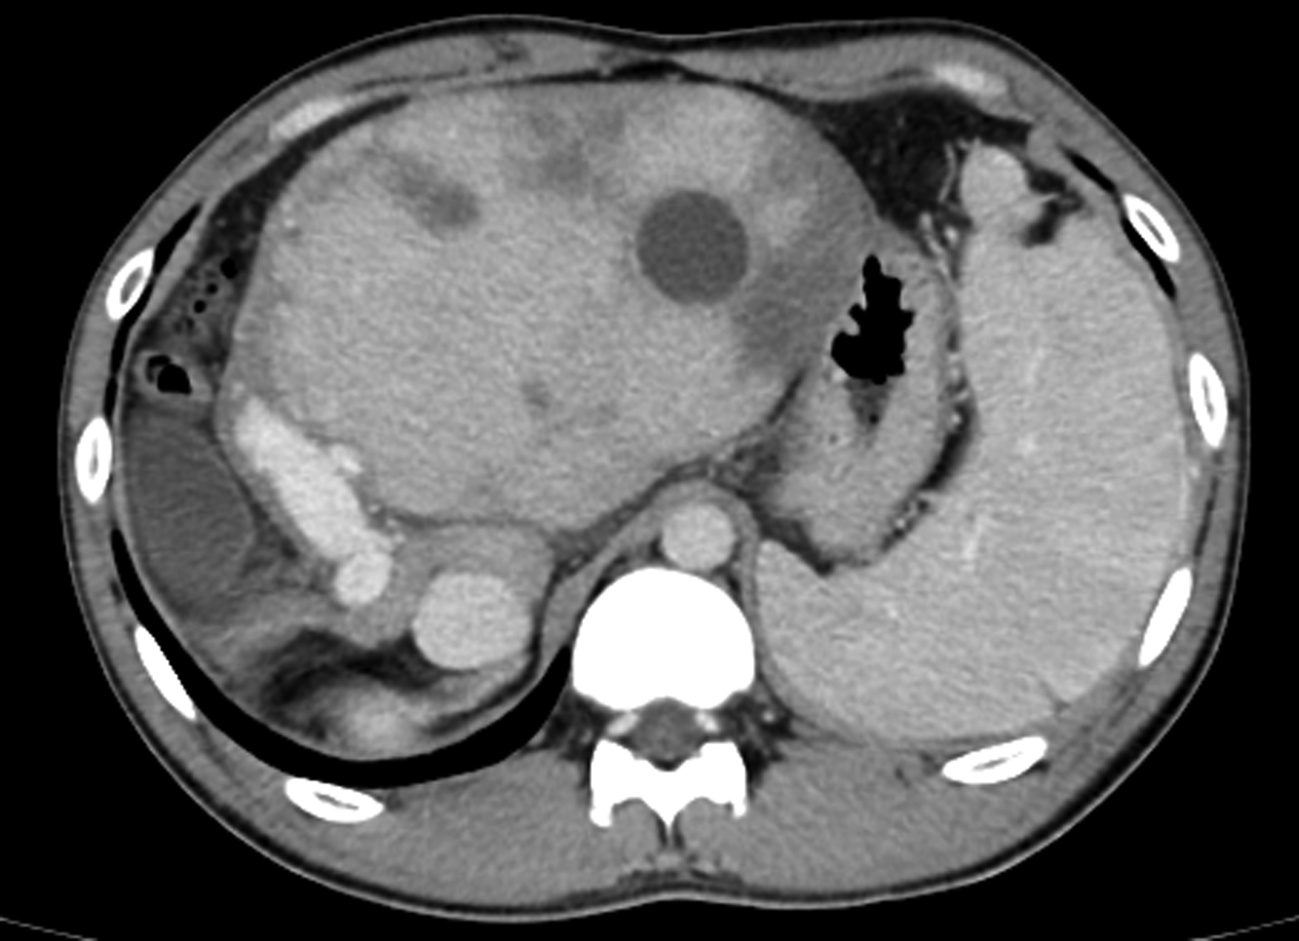

Short-term mortality and death causes after TACE in patients with primary liver cancer

Zhao LIU, Zhi LI, Kailun YANG, Siyin LI, Xiaoli ZHU, Caifang NI

2022, 38(11): 2510-2513. DOI: 10.3969/j.issn.1001-5256.2022.11.014

Abstract(1582) HTML (254) PDF (2070KB)(95)

Abstract:

Objective  To investigate the short-term mortality of transcatheter arterial chemoembolization (TACE) in patients with primary liver cancer, and explore the possible causes of death and countermeasures.  Methods  All patients who underwent TACE at the Department of Interventional Radiology, First Affiliated Hospital of Soochow University from January 2015 to December 2020 were studied, but those with metastatic liver cancer or receiving combined treatment were excluded. The clinical and imaging data of all patients were collected before and 30 days after TACE, and the clinical characteristics of the patients with short-term postoperative death were analyzed. Death within 30 days after TACE was defined as short-term death.  Results  A total of 1466 TACE in 741 patients with primary liver cancer were included. Ten patients (10/741, 1.35%) died within 30 days after TACE, with a mortality rate of 0.68% for all TACE. The mortality rate of d-TACE and c-TACE was 1.62% (3/185) and 0.55 % (7/1281), respectively. The mortality rates of patients at China Liver Cancer Staging Ⅰ, Ⅱ, and Ⅲ stages were 0.45% (2/448), 0.33% (2/599), and 1.43% (6/419), respectively. The mean diameter of the largest lesion in death cases was 10.1±0.8 cm. The possible causes of death were liver failure (4 cases), rupture bleeding (3 cases), myelotoxicity (1 case), pulmonary embolism (1 case), and heart failure (1 case).  Conclusion  The mortality rate after TACE in patients with primary liver cancer is low, with occasional short-term postoperative deaths. The death cases are characterized by a large tumor volume, and the most common causes of short-term death are liver failure and rupture bleeding.